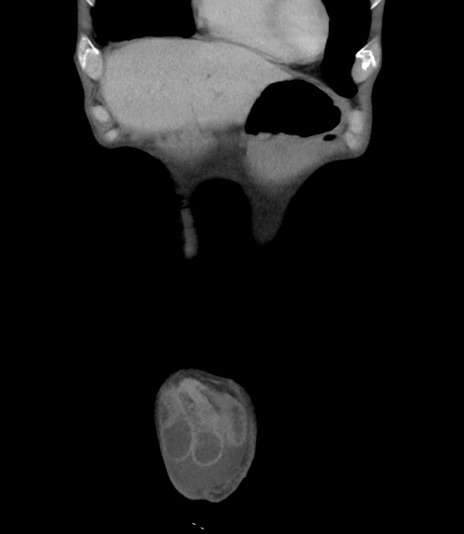

横断像

【症例】 70歳代男性

【主訴】右鼠径部腫瘤、疼痛

【既往歴】膀胱癌にて膀胱全摘、両側尿管皮膚瘻